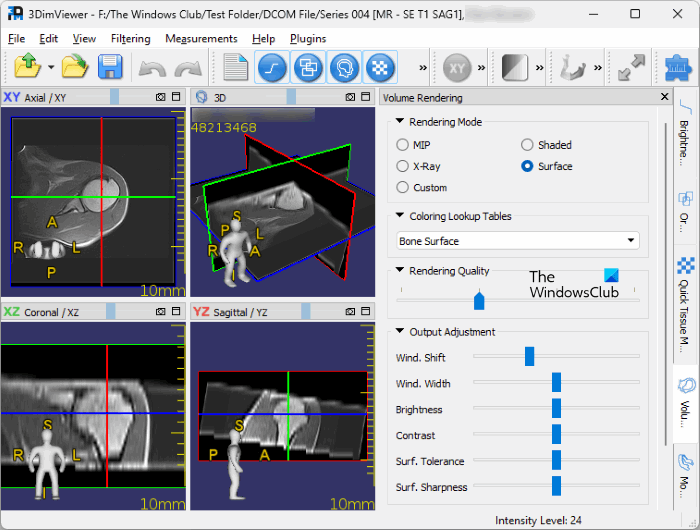

4] 3DimViewer

3DimViewer is one more free DICOM Viewer software on this list. It lets you view a DICOM image in both 2D and 3D modes. The 2D mode displays a separate view for all three planes, i.e., XY, YZ, and ZX. The 3D view shows the 3D image by combining all these three panes. You can enable and disable a particular plane in the 3D mode.

To view the DICOM file, you can select any of the following layouts:

- 3D View

- Tabs

- Grid

On the right side, you will find different tabs. These tabs have tools that let you perform different actions on the DICOM files. You can change the brightness and contrast levels of your DICOM image, The Ortho Slices tab lets you vary the position and value of three different planes.

The Measurements menu has two types of measurement tools, namely, intensity measurement and distance measurement. The default units to measure intensity and distance are Hu and mm respectively. You can also apply filters to your DICOM image. The following four types of filters are available in the software:

- Gaussian filter

- Median filter

- 3D Anisotropic filter

- Sharpening filter

You can save the edited DICOM image in DICOM format. I did not find the export option in the software. To download 3DimViewer, visit sourceforge.com.